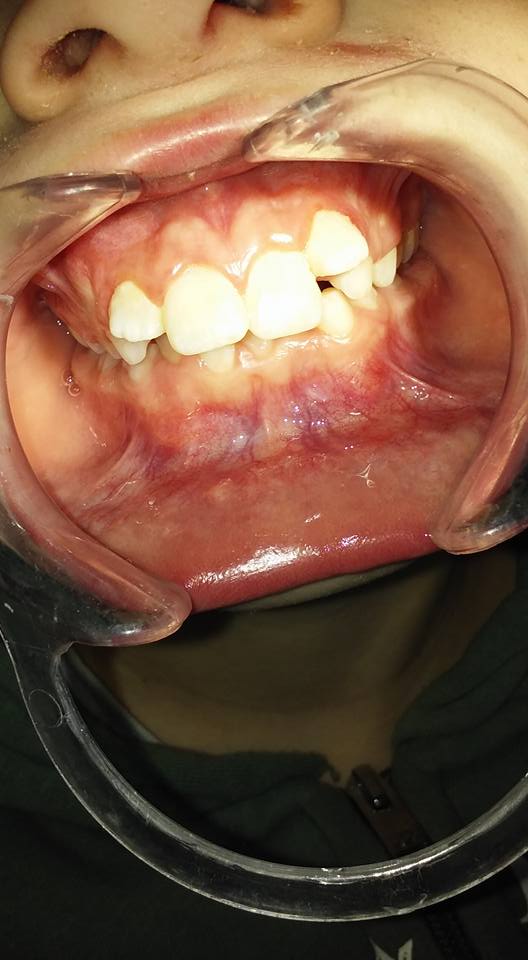

Nuestra misión es solucionar diferentes tipos de dolencias y/o problemas, tales como: caries, restauraciones, bruxismo, exodoncia, encías (gingivitis y/o periodontitis), ortodoncia, endodoncia y reposición de piezas dentarias.

Trabajamos con adultos y adolescentes desde 12 años. Atendemos a particulares.

HIGIENE Y ESTÉTICA BUCAL